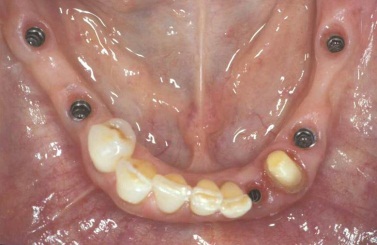

Během let může postupnou ztrátou zubů zůstat v ústech omezený počet zubů, které umožňují držení zubních náhrad.

V důsledku přetížení zbylých zubů např. houpavými pohyb snímacích náhrad dochází k uvolnění těchto zubů a držení můstků a protéz je tak velmi těžké. V těchto případech můžeme pomocí implantátů zvýšit počet pilířů a tím zabránit přetěžování a ztrátě zbylých zubů

Bezzubá čelist je hlavní indikací pro ošetření pomocí implantátů. Zejména celkové zubní náhrady v dolní čelisti mají velice nízkou stabilitu a držení díky velkému úbytku kosti.

S pomocí zubních implantátů můžeme díky různým kotevním systémům (třmeny, kulové hlavy, Locatory) zajistit stabilitu a držení protézy nebo při použití většího počtu implantátů zhotovit pevné náhrady – můstky nalepené nebo našroubované na pevno na implantáty.

S těmito typy náhrad můžeme dosáhnout perfektní funkci, výbornou estetiku, fonetiku a současně zajistit u pacienta možnost dobré hygienickou péče a čištění, která je pro životnost implantátů velice důležitá.